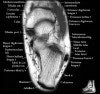

발목 관절의 MRI 단면 영상

- Coronal section

The coronal oblique T1 sequence follows the tendons of the ankle around the malleolar turns and also evaluates the medial ankle ligaments.

The coronal oblique PD fat suppressed sequence follows the tendons of the ankle around the malleolar turns and is particularly important in evaluation of the Posterior tibialis tendon.

Bone and marrow

Talar dome

Deltoid ligament

Tendons in arch

Plantar fascia

Troubleshoot ligaments